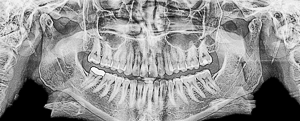

Кроме того, необходимо будет сделать рентгеновские снимки: ортопантомограмму (ОПТГ), телерентгенограммы(ТРГ). ОПТГ позволит судить о состоянии всех зубов, окружающих их костных тканях и наличии зачатков еще не прорезавшихся зубов. ТРГ — это рентгеновские снимки черепа выполненные по специальной методике, позволяющей получить снимок с размерами близкими к реальным. Так же на ТРГ различимы мягкие ткани головы (губы, нос, щеки). По ТРГ анализируется геометрия лица, выявляется характер и причина патологии, определяются допустимость и границы перемещений зубов, при этом оценивается изменение профиля лица пациента. После получения всех снимков врачу понадобится некоторое время для снятия геометрических замеров, выполнения математических расчетов и анализа результатов. Только после этого можно сделать заключение и подготовить окончательный план лечения. Возможны и другие анализы: например анализ рентгеновских снимков височно-нижнечелюстных суставов (ВНЧС). Так же перед началом лечения многие ортодонты проводят фотосъемку лица и ротовой полости. Фотография — отличный способ наглядно проследить динамику лечения и оценить достигнутый результат.